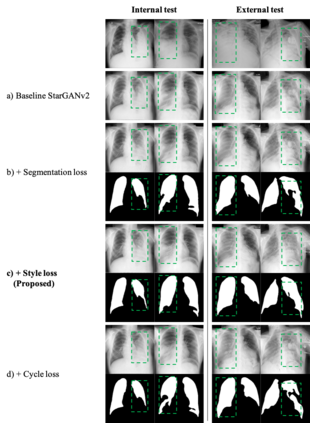

As the segmentation labels are scarce, extensive researches have been conducted to train segmentation networks without labels or with only limited labels. In particular, domain adaptation, self-supervised learning, and teacher-student architecture have been introduced to distill knowledge from various tasks to improve the segmentation performance. However, these approaches appear different from each other, so it is not clear how these seemingly different approaches can be combined for better performance. Inspired by the recent StarGANv2 for multi-domain image translation, here we propose a novel segmentation framework via AdaIN-based knowledge distillation, where a single generator with AdaIN layers is trained along with the AdaIN code generator and style encoder so that the generator can perform both domain adaptation and segmentation. Specifically, our framework is designed to deal with difficult situations in chest X-ray (CXR) segmentation tasks where segmentation masks are only available for normal CXR data, but the trained model should be applied for both normal and abnormal CXR images. Since a single generator is used for abnormal to normal domain conversion and segmentation by simply changing the AdaIN codes, the generator can synergistically learn the common features to improve segmentation performance. Experimental results using CXR data confirm that the trained network can achieve the state-of-the art segmentation performance for both normal and abnormal CXR images.